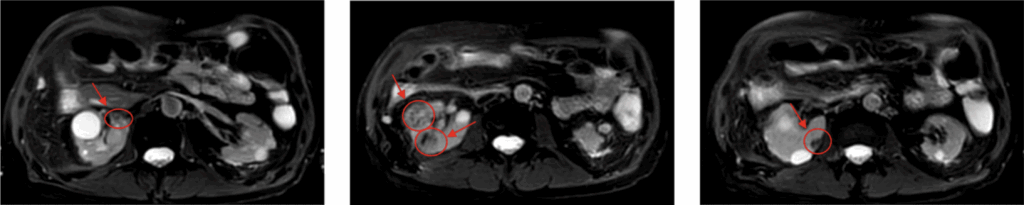

Planning3 mm PTV margin; no CTV margin used (Figure 3)

Figure 3: Treatment planning in axial and coronal views for four RCC lesions

Follow-upStable disease confirmed by MRI at 29 month follow-up